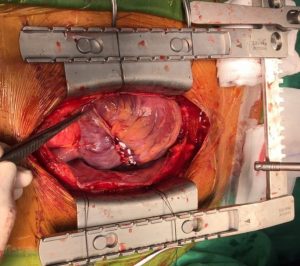

Ngày 10/02/2017, Khoa Phẫu thuật Tim Mạch – Lồng ngực- Bệnh viện Đa khoa Xuyên Á (BVXA) vừa cứu sống bệnh nhân T.T (sinh năm 1979, ngụ tại Huyện Hóc Môn, TP.HCM) bị chấn thương ngực kín gây vỡ buồng tim.